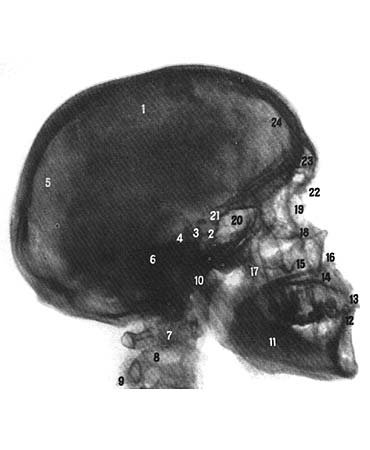

Височная кость, os temporale, парная, участвует в образовании основания черепа и боковой стенки его свода. В ней залегает орган слуха и равновесия. Она сочленяется с нижней челюстью и является опорой жевательного аппарата. На наружной поверхности кости имеется наружное слуховое отверстие, porus acusticus externus, вокруг которого располагаются три части височной кости: сверху — чешуйчатая часть, pars squamosa, кнутри и сзади — каменистая часть (пирамида), pars petrosa, спереди и снизу — барабанная часть, pars tympanica. Чешуйчатая часть, pars squamosa, имеет форму пластинки и располагается почти в сагиттальном направлении. Наружная височная поверхность, facies temporalis, чешуи немного шероховата и слегка выпукла. В заднем отделе ее проходит в вертикальном направлении борозда средней височной артерии, sulcus arteriae temporalis mediae (след прилегания одноименной артерии). В задненижнем отделе чешуйчатой части имеется дугообразная линия, которая продолжается в нижнюю височную линию теменной кости. От чешуйчатой части, выше и несколько кпереди наружного слухового отверстия, отходит в горизонтальном направлении скуловой отросток, processus zygomaticus. Начинаясь широким корнем, скуловой отросток затем суживается. Он имеет внутреннюю и наружную поверхности и два края — верхний, более длинный, и нижний, более короткий. Передний конец скулового отростка зазубрен и соединяется с височным отростком, processus temporalis, скуловой кости, образуя с ним скуловую дугу, arcus zygomaticus. На нижней поверхности корня находится поперечноовальной формы суставная нижнечелюстная ямка, fossa mandibularis, куда входит сочленяющаяся с ней головка нижней челюсти. Впереди суставную ямку ограничивает суставной бугорок, tuberculum articulare. Наружная поверхность чешуйчатой части участвует в образовании височной ямки, fossa temporalis (здесь начинаются пучки височной мышцы, m. temporalis).Внутренняя, мозговая, поверхность чешуи, facies cerebralis, слегка вогнута. На ней имеются пальцевые вдавления, impressio-nes digitatae, и мозговые возвышения, а также артериальная борозда, sulcus arteriosus (в ней залегает средняя менингеаль-ная артерия, a. meningea media). Чешуйчатая часть височной кости имеет два свободных края — клиновидный и теменной. Передненижний, клиновидный край, margo sphenoidalis, широкий, зубчатый, соединяется с чешуйчатым краем большого крыла клиновидной кости и образует клиновидно-чешуйчатый шов, sutura sphenosquamosa. Верхнезадний, теменной край, margo parietalis, заострен, длиннее предыдущего, соединяется с чешуйчатым краем теменной кости. Каменистая часть, pars petrosa (пирамида), височной кости состоит из заднелатерального и переднемедиального отделов. Заднелатеральным отделом каменистой части височной кости является сосцевидный отросток, processus masloideus, который располагается кзади от наружного слухового отверстия; на нем различают наружную и внутреннюю поверхности. Наружная поверхность выпукла, шероховата и является местом прикрепления мышц. Книзу сосцевидный отросток переходит в конусообразной формы выступ, который хорошо прощупывается через кожу. С внутренней стороны отросток ограничен глубокой сосцевидной вырезкой, incisura mastoidea (от нее берет начало заднее брюшко двубрюшной мышцы, venter posterior m. digastrieus). Параллельно вырезке и несколько кзади располагается борозда затылочной артерии, sulcus arteriae occipitalis (след прилегания одноименной артерии). У основания сосцевидного отростка, на его наружной поверхности, нередко имеется сосцевидное отверстие, foramen mastoideum; иногда оно находится в шве. соединяющем сосцевидный отросток с затылочной костью, и принадлежит к числу венозных выпускников. На внутренней, мозговой, поверхности сосцевидного отростка проходит широкая S-образной формы борозда сигмо-Impresslo trigemiiil видного синуса, sulcus sinus sigmoidei, переходящая вверху в одноименную борозду теменной кости и далее в борозду поперечного синуса затылочной кости (в ней залегает одноименный венозный синус твердой мозговой оболочки). Книзу борозда сигмовидного синуса продолжается в одноименную борозду затылочной кости. Сзади сосцевидный отросток ограничен зазубренным затылочным краем, margo occipitalis, который, соединяясь с сосцевидным краем затылочной кости, образует затылочно-сосцевидный шов. sutura occipitomastoidea. В этом шве, на середине его длины или в затылочном крае, находится сосцевидное отверстие, foramen mastoideum (иногда их бывает несколько), которое, как уже упоминалось, является местом залегания сосцевидных эмиссарных вен, vv. emissariae mastoideae, соединяющих подкожные вены головы с сигмовидным венозным синусом, и сосцевидной ветви затылочной артерии, ramus mastoi-deus a. occipitalis. Сверху сосцевидный отросток ограничен теменным краем, который на границе с одноименным краем чешуи височной кости образует теменную вырезку, incisura parietalis; сюда входит сосцевидный угол теменной кости, образуя теменно-сосцевидный шов, sutura parietomastoidea. У места перехода наружной поверхности сосцевидного отростка в наружную поверхность чешуи можно заметить остатки чешуйчато-сосцевидного шва, sutura squamosomasoidea, который хорошо выражен на черепе детей. На распиле сосцевидного отростка видны находящиеся внутри него костные воздухоносные полости — сосцевидные ячейки, cellulae mastoideae, отделяющиеся одна от другой костными стенками. Постоянной полостью является сосцевидная пещера, antrum mastoideum, залегающая в центральной части отростка; в нее открываются сосцевидные ячейки, и она соединяется с барабанной полостью. Сосцевидные ячейки и сосцевидная пещера выстланы слизистой оболочкой. Переднемедиальный отдел каменистой части лежит кнутри от чешуйчатой части и сосцевидного отростка. Он имеет форму трехгранной пирамиды, длинная ось которой направлена снаружи и сзади и вперед. Основание каменистой части обращено кнаружи и кзади; верхушка пирамиды, apex partis petrosae. направлена кнутри и кпереди. В каменистой части различают три поверхности: переднюю, заднюю и нижнюю, и три края: верхний, задний и передний. Передняя поверхность пирамиды, facies anterior partis pertosae, обращена в полость черепа, гладкая и широкая, направляется косо сверху вниз и наперед и переходит в мозговую поверхность чешуйчатой части, от которой она иногда отделяется каменисто-чешуйчатой щелью, fissura petrosquamosa. Почти на середине передней поверхности имеется дугообразное возвышение, eminentia arcuata, которое образуется залегающим под ним передним полукружным каналом лабиринта. Между возвышением и каменисто-чешуйчатой щелью располагается небольшая площадка — крыша барабанной полости, legmen tympani. под которой находится барабанная полость, cavum tym-pani. На передней поверхности вблизи верхушки каменистой части имеется небольшое тройничное вдавление, impressio tri-gemini (место прилегания узла тройничного нерва). Латерально от вдавления располагается расщелина канала большого каменистого нерва, hiatus canalis nervi pelrosi majoris. от которого медиально направляется узкая борозда большого каменистого нерва, sulcus nervi petrosimajoris. Кпереди и несколько латерально от указанного отверстия находится небольшая расщелина канала малого каменистого нерва, hiatus canalis nervi petrosi minoris, от которого направляется борозда малого каменистого нерва, sulcus nervi petrosi minoris. Задняя поверхность пирамиды, facies posterior partis petrosae, так же как и передняя поверхность, обращена в полость черепа, но направляется вверх и кзади, где переходит в сосцевидный отросток. Почти на середине ее находится округлой формы внутреннее слуховое отверстие, porus acusticus internus, которое ведет во внутренний слуховой проход, meatus acusticus internus (в нем лежат лицевой, промежуточный, пред-дверноулитковый нервы, а также артерия и вена лабиринта, a. et v. labirinthi). Немного выше и латерально от внутреннего слухового отверстия имеется хорошо выраженная у новорожденных небольшой глубины поддуговая ямка, fossa subarcuata (в нее входит отросток твердой мозговой оболочки).Еще латеральное от внутреннего слухового отверстия залегает щелевидной формы наружная апертура водопровода преддверия, apertwa externa aquaeductus vestibuli (через него из полости внутреннего уха выходит эндолимфатический проток).Нижняя поверхность пирамиды, facies inferior partis petrosae, шероховата и неровна, залегает на нижней поверхности основания черепа. На ней располагается округлой или овальной формы яремная ямка, fossa jugularis (место прилегания верхней луковицы внутренней яремной вены).На дне этой ямки находится небольшая борозда (в ней проходит ушная ветвь блуждающего нерва). Борозда ведет в отверстие сосцевидного канальца. canaliculus mastoideus, который открывается в барабанно-сосиевиднои щели, fissura tym-panomastoidea.Задний край яремной ямки ограничен яремной вырезкой, incisura jugularis, которую небольшой внутрияремный отросток, processus intrajugularis. разделяет на две части: передне-медиальную и заднелатеральную. Кпереди от яремной ямки залегает округлой формы отверстие; оно ведет в сонный канал. canalis caroticus, открывающийся на вершине каменистой части отверстием. Между передней окружностью яремной ямки и наружным отверстием сонного канала имеется небольшой величины каменистая ямочка, fossula petrosa (место прилегания нижнего узла языкоглоточного нерва). В глубине ямочки находится отверстие, открывающее ход в барабанный канадец, canaliculus tympanicus (в нем проходят барабанный нерв и нижняя барабанная артерия). Барабанный канадец ведет в среднее ухо, auris media, или барабарную полость, cavum tympani. Латерально от яремной ямки выступает направленный книзу и несколько кпереди различной длины шиловидный отросток, processus styloideus. от которого начинаются мышцы и связки. Впереди и снаружи корня отростка спускается костный выступ барабанной части — влагалище шиловидного отростка, vagina processus slyloidei. Позади корня отростка имеется шило-сосцевидное отверстие, foramen stylomastoideum, которое является выходным отверстием лицевого канала, canalisfacialis. Верхний край пирамиды, margo superior partis petrosae, отделяет ее переднюю поверхность от задней. Вдоль края проходит борозда верхнего каменистого синуса, sulcus sinus petrosi superioris — отпечаток лежащего здесь верхнего каменистого венозного синуса и прикрепления намета мозжечка — части твердой мозговой оболочки. Эта борозда переходит кзади в борозду сигмовидного синуса сосцевидного отростка височной кости. Задний край пирамиды, margo posterior partis petrosae, отделяет заднюю ее поверхность от нижней. Вдоль него, на мозговой поверхности, проходит борозда нижнего каменистого синуса, sulcus sinus petrosi inferioris (след прилегания нижнего каменистого венозного синуса). Почти на середине заднего края, вблизи яремной вырезки, находится треугольной формы воронкообразное углубление, в котором лежит наружная апертура канальца улитка, apertura externa canaliculi cochleae. Передний край каменистой части, расположенный с латеральной стороны ее передней поверхности, короче верхнего и заднего; он отделен от чешуйчатой части височной кости каменисто-чешуйчатой щелью, fisswa petrosquamatosa. На нем, латерально от внутреннего отверстия сонного канала, располагается отверстие мышечно-трубного канала, canalis mus-culolubarius, ведущее в барабанную полость (см. Мышечно-трубный канал).